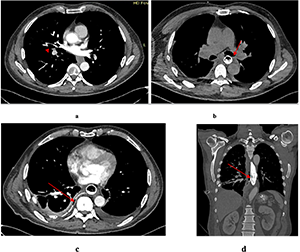

Chest, abdomen, and pelvis CT scan with intravenous enhancement demonstrated a mass originating from the esophageal wall (Fig. 1).

Contrast-enhanced CT of the chest, abdomen, and pelvis showed circumferential thickening and distortion of the abdominal esophagus and gastric cardia, with a mass measuring 48×78 mm and a density of 60-63 Hounsfield units (Fig. 4). perigastric lymph nodes were not radiologically visible. Isolated para-aortic lymph nodes up to 13 mm were noted.

A barium swallow demonstrated a round filling defect on the posterior wall of the lower third of the esophagus, measuring 39×29 mm, with well-defined margins and intramural calcifications. Contrast-enhanced CT of the chest, abdomen, and pelvis showed a well-circumscribed lesion measuring 25×22×30 mm in the middle third of the esophagus, narrowing the esophageal lumen to a slit-like configuration. The external contour of the esophageal wall remained intact (Fig. 8a).